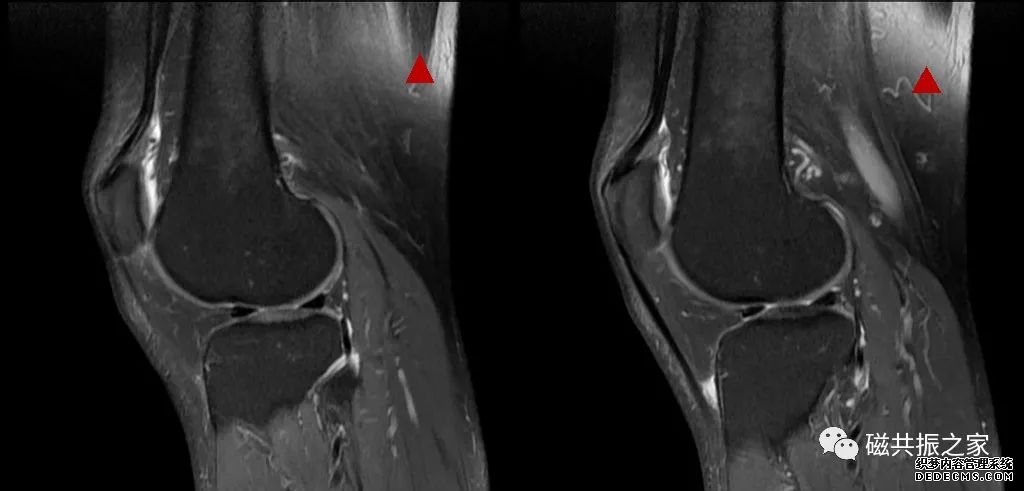

如上图△,一例膝关节的扫描,扫描技师称患者身上的金属已去除完全,患者体内无任何金属植入物,但图像的局部区域还是存在压脂均匀的情况,是偏中心的问题、线圈的贴合性较差还会其它原因引起的?看到这样的图像表现,首先还是考虑是金属异物导致的,由于异物不在成像的视野内,虽然在其定位像和校准图像中均看不到相关的异常信号表现,但我们可以通过对其怀疑有问题的区域进行一次校准扫描,以此来验证是否有金属异物的存在,如下图▽。

在校准序列图像中可见到右侧有类似金属异物导致的异常信号表现,最终证实是有由于患者磁疗裤上的小磁块导致。

在MRI扫描中,校准序列作为扫描时间短,不易变形,扫描范围及视野大等特点,是识别金属异物及其位置的有效途径之一。

虽然校准序列的信噪比不高,但能从图像上比较准确地识别出金属异物及其位置。甚至可以根据图像中伪影出现的区域、范围、表现形式等大体地评估对最终图像带来的影响,并对我们的后续扫描做出相应的调整。